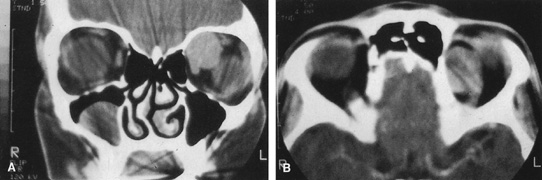

Fig. 16. A. Patient with right orbital cellulitis. B. Coronal CT scan demonstrating subperiosteal abscess formation from frontal and ethmoidal sinusitis. C. Frontoethmoidal orbitotomy incision marked for abscess drainage.

The periosteum is exposed and incised with a Freer elevator and then is reflected off the bone posteriorly. It is generally quite adherent to the curved contour of the medial canthal bones, especially at the medial canthal tendon. The anterior lacrimal crest is encountered inferiorly. Care should be taken not to damage the lacrimal sac with the elevator. The posterior lacrimal crest is visible behind the sac. Adequate mobilization of the periosteal connections to the anterior lacrimal crest gives a large area of exposure. The periosteal elevation is carried superiorly in the area of the trochlea. Elevation of the periosteum opens the subperiosteal space. Blood or pus caused by fracture or infection, if present in this space, is encountered at this point.

Elevation of the periorbita along the medial orbital wall posterior to the lacrimal sac progresses easily. Orbital fractures involving the thin ethmoid bone are seen at this point. The anterior ethmoidal artery is seen at the junction of the ethmoidal and frontal bones where the orbital roof meets the medial orbital wall (see Fig. 7). Usually it is found on a line extending posteriorly from the superior border of the medial canthal tendon. This artery either should be thoroughly cauterized with the bipolar cautery or clipped with a vascular clip before cutting. As the dissection in the subperiosteal space moves posteriorly, the orbit narrows. The posterior ethmoidal artery is identified. This is a reliable landmark for the optic foramen, which lies approximately 5 mm behind the ethmoidal artery.

Indications

The frontoethmoidal medial orbitotomy allows access for a variety of procedures in the subperiosteal and peripheral surgical spaces and sinuses (Fig. 17). Its main use is for processes involving both the frontal or ethmoid sinuses and the orbit. Entrance into the subperiosteal space is obtained easily. Drainage of subperiosteal blood or pus occurs as the space is entered.

Fig. 17. Schematic demonstration of areas amenable to frontoethmoidal orbitotomy. Coronal (A) and axial (B) views. This approach can be used for exposure of the medial orbit, ethmoid and sphenoid sinuses, and optic canal.